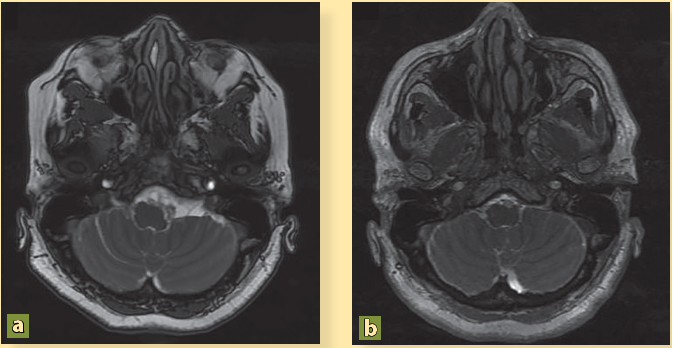

La paciente presenta mejoría clínica y es egresada por remisión de la cefalea y de las crisis convulsivas tras 16 días de estancia hospitalaria con indicaciones de continuar con esteroides vía oral y fármacos anticomiciales. Por iniciativa propia, la paciente no acudió a sus citas de seguimiento durante 4 años. Después, y debido a que ha presentado cefalea con intensidad 10/10, náusea y vómito constantes, desorientación y alteraciones del lenguaje, y varios episodios convulsivos, es traída por sus familiares al servicio de urgencias. Los familiares informaron que el tratamiento médico fue abandonado y optaron por una terapia de medicina naturista. Se ingresó la paciente y la nueva RM mostró persistencia de los cisticercos (figuras 2A, 2C, 3A, 4A) así como dilatación de los ventrículos (figura 5A). Se colocó una derivación ventrículo peritoneal (DVP) (figura 5B) y se inició nuevo tratamiento con albendazol (15 mg/kg), praziquantel (50 mg/kg) por 10 días, y dexametasona (8 mg/8h). Tras 40 días de estancia hospitalaria, se decidió su egreso con cita en la consulta externa.

En a y c se observan imágenes quísticas a nivel del espacio subaracnoideo adyacente al giro temporal superior y en la cisterna pontina, compatibles con NCC, mientras que en b y d han desaparecido después del tratamiento con albendazol.

Figura 2 Resonancia magnética secuencia FIESTA